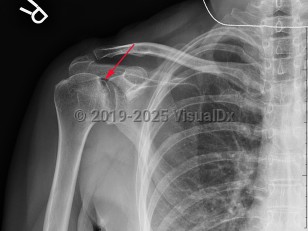

Grade / classification system: Cruess classification

- Stage 3 – crescent sign (subchondral fractures) on x-ray